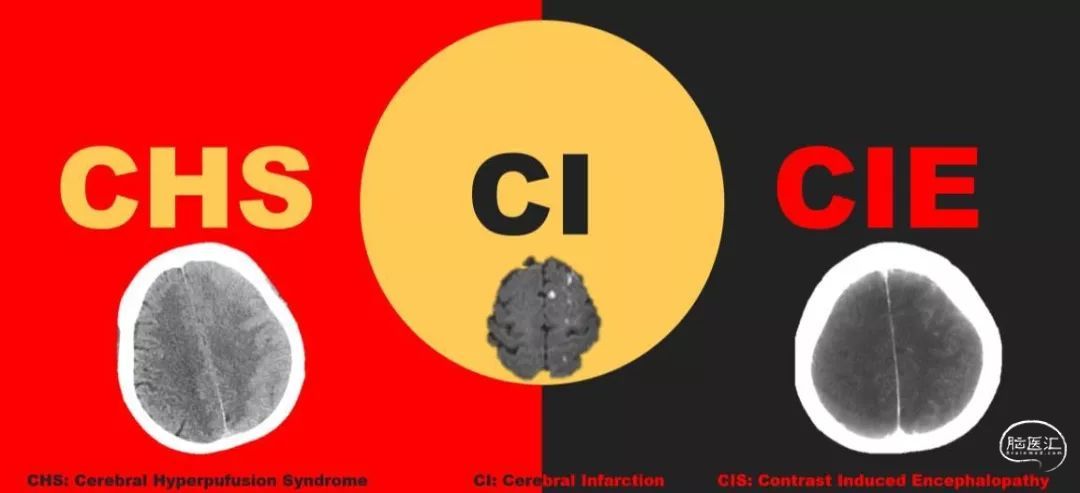

颈动脉血管成形支架植入术后即刻出现神经功能缺损,有哪几种可能呢?三个“C”,三种并发症需要考虑。

1

Cerebral Infarction

2

Cerebral Hyperpufusion Syndrome

3

Contrast Induced Encephalopathy